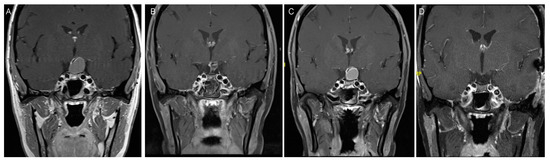

3.2. Clinical Presentation

3.3. Management and Outcome